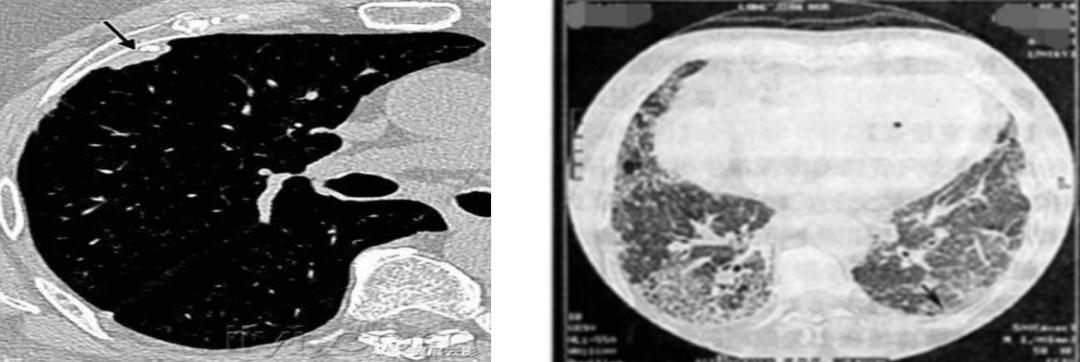

12、胸部CT:右肺中下叶团块、索条灶,右侧胸腔积液(图2)。

图2:胸部CT(2019年08月12日)

1、胸部动脉成像(CTA)(2019-08-14):右肺中下叶团块、条索灶,右侧胸腔积液,较2019-8-12老片积液增多,CTA未见明显充盈缺损(图3)。

(左 2019-08-12;右 2019-08-14)

图3:胸部动脉成像(CTA)(2019-08-14)